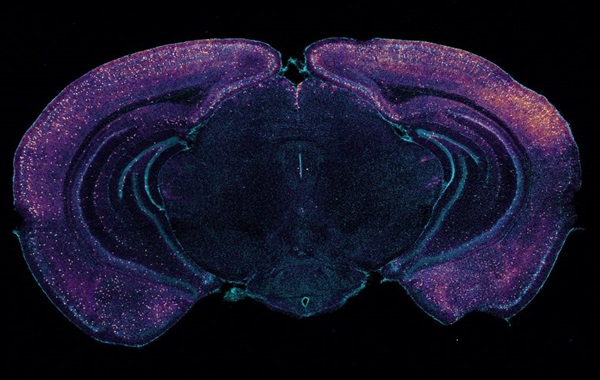

In a new study in Nature using a mouse model of the disease, researchers at The Picower Institute for Learning and Memory of MIT reveal a key mechanism that may contribute to these beneficial effects: clearance of amyloid proteins, a hallmark of AD pathology, via the brain’s glymphatic system, a recently discovered “plumbing” network parallel to the brain’s blood vessels.

Working with “5XFAD” mice, which genetically model Alzheimer’s, Murdock and co-authors first replicated the lab’s prior results that 40 Hz sensory stimulation increases 40 Hz neuronal activity in the brain and reduces amyloid levels. Then they set out to measure whether there was any correlated change in the fluids that flow through the glymphatic system to carry away wastes. Indeed, they measured increases in cerebrospinal fluid in the brain tissue of mice treated with sensory gamma stimulation compared to untreated controls. They also measured an increase in the rate of interstitial fluid leaving the brain. Moreover, in the gamma-treated mice, he measured increased diameter of the lymphatic vessels that drain away the fluids and measured increased accumulation of amyloid in cervical lymph nodes, which is the drainage site for that flow.